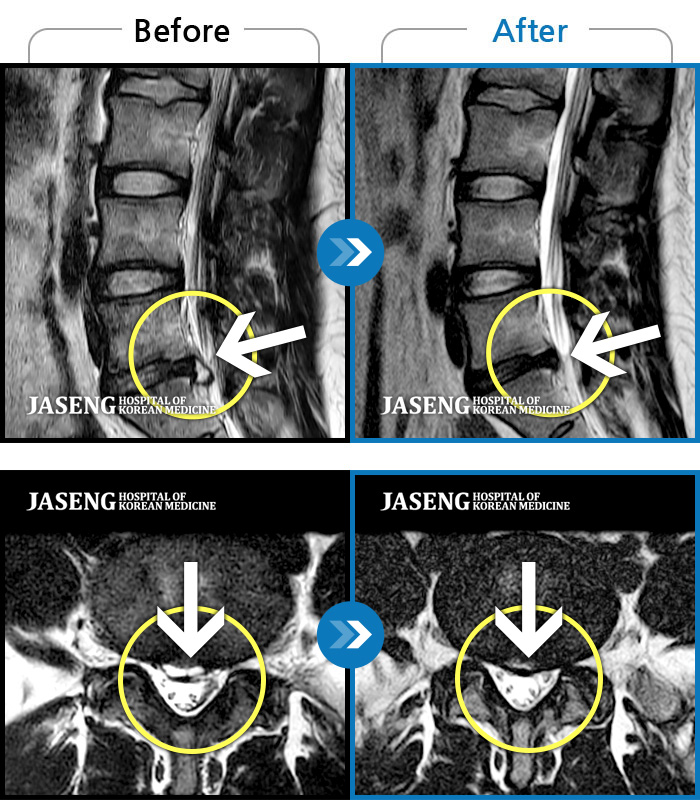

허리디스크

천안 · 김세정 원장

좌측 다리 저림이 매우 심해 야간통증 및 일상 생활에 제한이 많은 상태로 내원하였습니다.

촬영시기

2021.08.07 ~ 2024.07.22